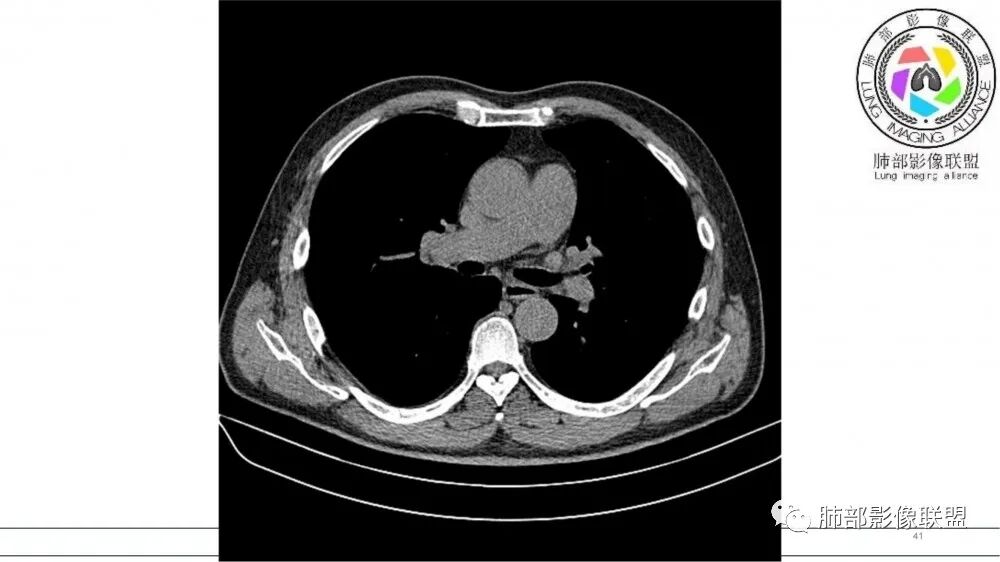

左肺上叶前段支气管内铸形生长软组织影,增强后均匀强化,远侧见斑片状磨玻璃影。考虑恶性病变,粘表?粘液腺?

左肺上叶前段支气管杵状指样扩张,内见实性组织阻塞性,并强化明显,边缘饱满,周边多发小斑点影,小花小草征,老年男性,长期吸烟史,方向恶性,首选支气管内浸润鳞Ca可能性大。

左肺上叶尖后段支气管近端截断,远端见高密度铸型,远侧见阻塞性改变,老年男性,吸烟史,考虑恶性,鳞癌。ABPA代排

指套征,扩张支气管内软组织强化,远侧肺野阻塞性炎,纵隔、左肺门肿大淋巴结;老年男性,吸烟,考虑鳞癌,鉴别小

指套征:是影像征象,胸部平片表现为手指状密度增高影,以肺门为中心呈放射状分布,CT显示扩张支气管内低密度黏液栓形成或实性病变,呈管状、树枝状或卵圆形密度增高影;支气管扩张伴近端梗阻时,扩张支气管内部黏液分泌物不能排出而形成。可以伴随远端空气潴留征、阻塞性炎症。

研究报道,中心型 SCLC 经 CT 扫描后通常支气管表现为鼠尾样狭窄,肺门或纵隔肿块明显,由于肿块沿管壁生长表现为顺延支气管形态的不规则形状。病灶相对特征性影像学表现比如鸭蹼状、腊肠状、葫芦状及葡萄状改变,可以出现血管包埋,很少有空洞、空泡,较少引发肺不张,阻塞性炎症成都较轻。与一般肺癌比较,恶性程度高,侵袭力强、病灶很小就容易远处转移!Herzberg 等[19]研究指出,20%以上 SCLC 倍增时间短,预后不良。